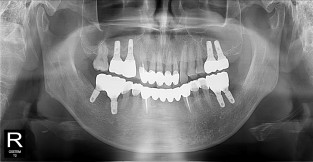

풀케이스

치료기간 : 2022-03-18 ~ 2023-09-15

1. 상기 x-ray 이미지 모두 동일한 해당 의료기관에서 진료한 환자입니다.

2. 상기 x-ray 이미지 모두 동일 인물의 것입니다.

3. 치료 전 이미지는 2022-03-18에 촬영했으며, 치료 후 이미지는 2023-09-15에 촬영하였습니다.

4. 상기 x-ray 이미지 모두 동일 조건에서 환자분의 동의를 받아촬영되었습니다.

* 임플란트 시술은 환자분의 상태(고혈압, 당뇨 등)에 따라 부작용이 있을 수 있으니, 반드시 전문의와 상담이 필요합니다.

* 임플란트 수술 부작용

: 수술 후 출혈, 교합, 통증, 붓기, 염증 등의 문제점이 발생할 수 있습니다.)